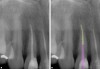

Fig 5. Radiograph of file in the canal verifying path to WL.

Figure 5